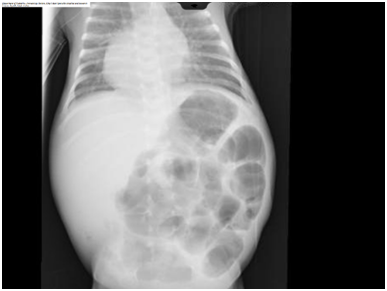

A male infant, twin B was born at 32weeks’ gestation by cesarean section due to fetal distress to a 26year old gravida 2 and Para 1 mother. The antenatal ultrasound of our patient showed congenital heart disease. The maternal history was insignificant. He weighed 1880grams and had Apgar scores of 9 and 9 at 1 and 5minutes respectively. He developed respiratory distress immediately after birth and required intubation and mechanical ventilation. There was no dysmorphic features. Echocardiogram and C.T cardiac with contrast showed dextrocardia, trunk’s arteriosus, interrupted aortic arch, large ventricular septal defect and patent ductus arteriosus. He was clinical stable and was started on enteral feeds. He had episode of gastric aspirates but they were considered insignificant. At two weeks of age he became septic with abdominal distension. He required dobutamin to restore his low blood pressure. Abdominal radiographs showed gastric and intestinal pneumatosis without any evidence of free intraperitoneal or portal venous air (Figure 1). Leukopenia and thrombocytopenia were present. He was started on antibiotics (ampicillin, gentamicin and metronidazole). He passed bloody stools with mucous. He required several platelet transfusions to correct the severe thrombocytopenia. The septic workup showed sterile blood cultures. His abdominal radiographs improved on day five of treatment (Figure 2). His head ultrasound was normal. The clinical condition of the infant significantly improved.

Figure 2 Abdominal X-ray of our patient after 5 days of treatment showing no gastric and intestinal pneumatosis.